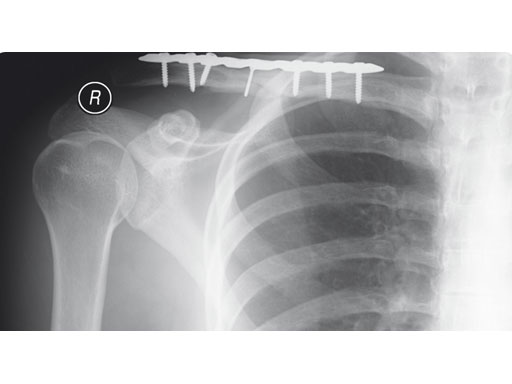

A 22-year-old man sustained an open clavicle fracture after a motorcycle injury.

Fig 2ab Postoperative images.

Fig 3ab X-rays taken 3 months postoperatively.

Case provided by Harry A Hoyen III, Cleveland, USA